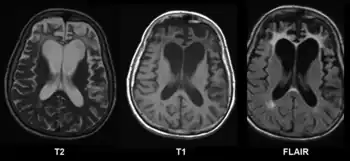

Structural MRI scans often reveal frontal lobe and/or anterior temporal lobe atrophy but in early cases the scan may seem normal. Atrophy can be either bilateral or asymmetric.[27] Registration of images at different points of time (e.g., one year apart) can show evidence of atrophy that otherwise (at individual time points) may be reported as normal. Many research groups have begun using techniques such as magnetic resonance spectroscopy, functional imaging and cortical thickness measurements in an attempt to offer an earlier diagnosis to the FTD patient. Fluorine-18-fluorodeoxyglucose positron emission tomography (FDG-PET) scans classically show frontal and/or anterior temporal hypometabolism, which helps differentiate the disease from Alzheimer's disease. The PET scan in Alzheimer's disease classically shows biparietal hypometabolism. Meta-analyses based on imaging methods have shown that frontotemporal dementia mainly affects a frontomedial network discussed in the context of social cognition or 'theory of mind'.[28] This is entirely in keeping with the notion that on the basis of cognitive neuropsychological evidence, the ventromedial prefrontal cortex is a major locus of dysfunction early on in the course of the behavioural variant of frontotemporal degeneration.[29] The language subtypes of frontotemporal lobar degeneration (semantic dementia and progressive nonfluent aphasia) can be regionally dissociated by imaging approaches in vivo.[30]